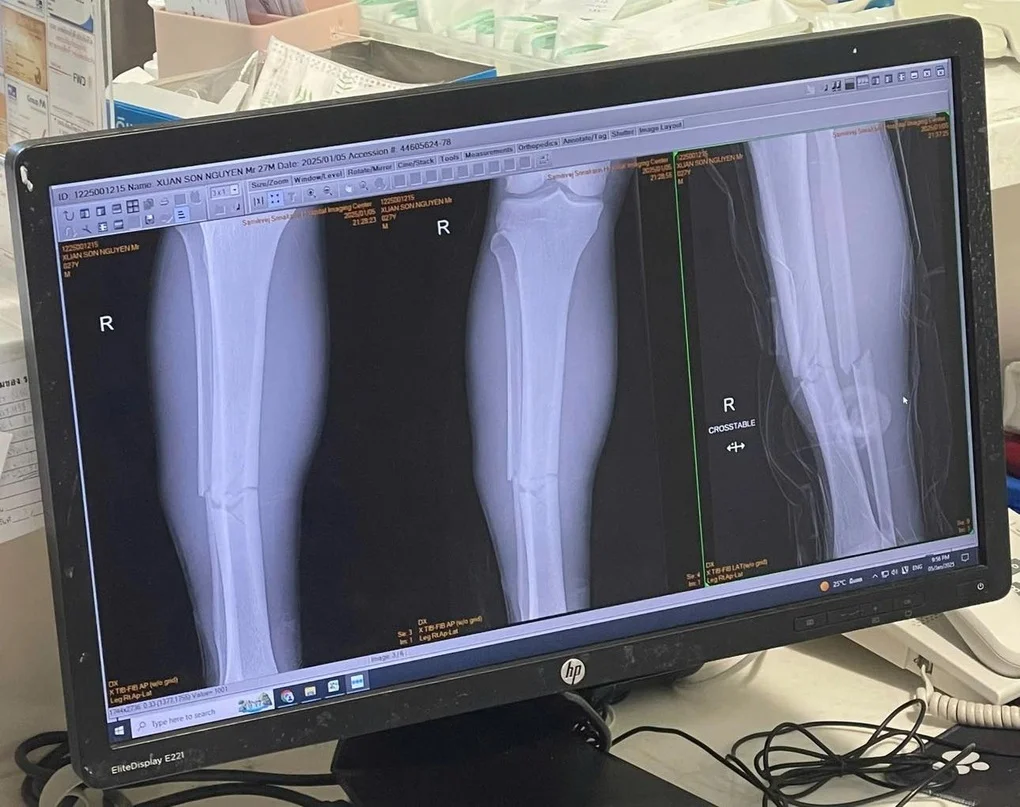

Theo như kết quả chụp chiếu thì Xuân Son đã bị gãy 2 xương ở chân phải, đồng thời cầu thủ này của chúp ta chắc chắn sẽ phải nghỉ thi đâu trong nhiều tháng tới.

Kết quả xét nghiệm tại bệnh viện cho biết Xuân Son đã gãy 2 xương ở ống chân phải. Điều trị và hồi phục của tiền đạo số 12 sẽ mất nhiều thời gian. Hiện chưa rõ Xuân Son có thể trở lại thi đấu thi đấu vào thời điểm nào.